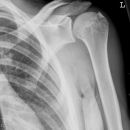

Subcapitale Fraktur und Tuberculum majus